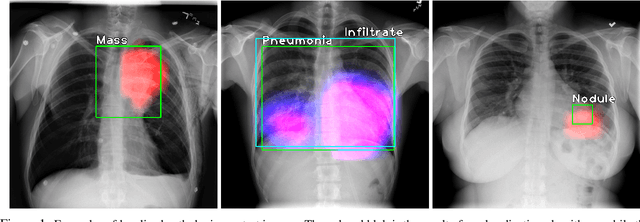

Localization of an object within an image is a common task in medical imaging. Learning to localize or detect objects typically requires the collection of data which has been labelled with bounding boxes or similar annotations, which can be very time consuming and expensive. A technique which could perform such learning with much less annotation would, therefore, be quite valuable. We present such a technique for localization with limited annotation, in which the number of images with bounding boxes can be a small fraction of the total dataset (e.g. less than 1%); all other images only possess a whole image label and no bounding box. We propose a novel loss function for tackling this problem; the loss is a continuous relaxation of a well-defined discrete formulation of weakly supervised learning and is numerically well-posed. Furthermore, we propose a new architecture which accounts for both patch dependence and shift-invariance, through the inclusion of CRF layers and anti-aliasing filters, respectively. We apply our technique to the localization of thoracic diseases in chest X-ray images and demonstrate state-of-the-art localization performance on the ChestX-ray14 dataset.